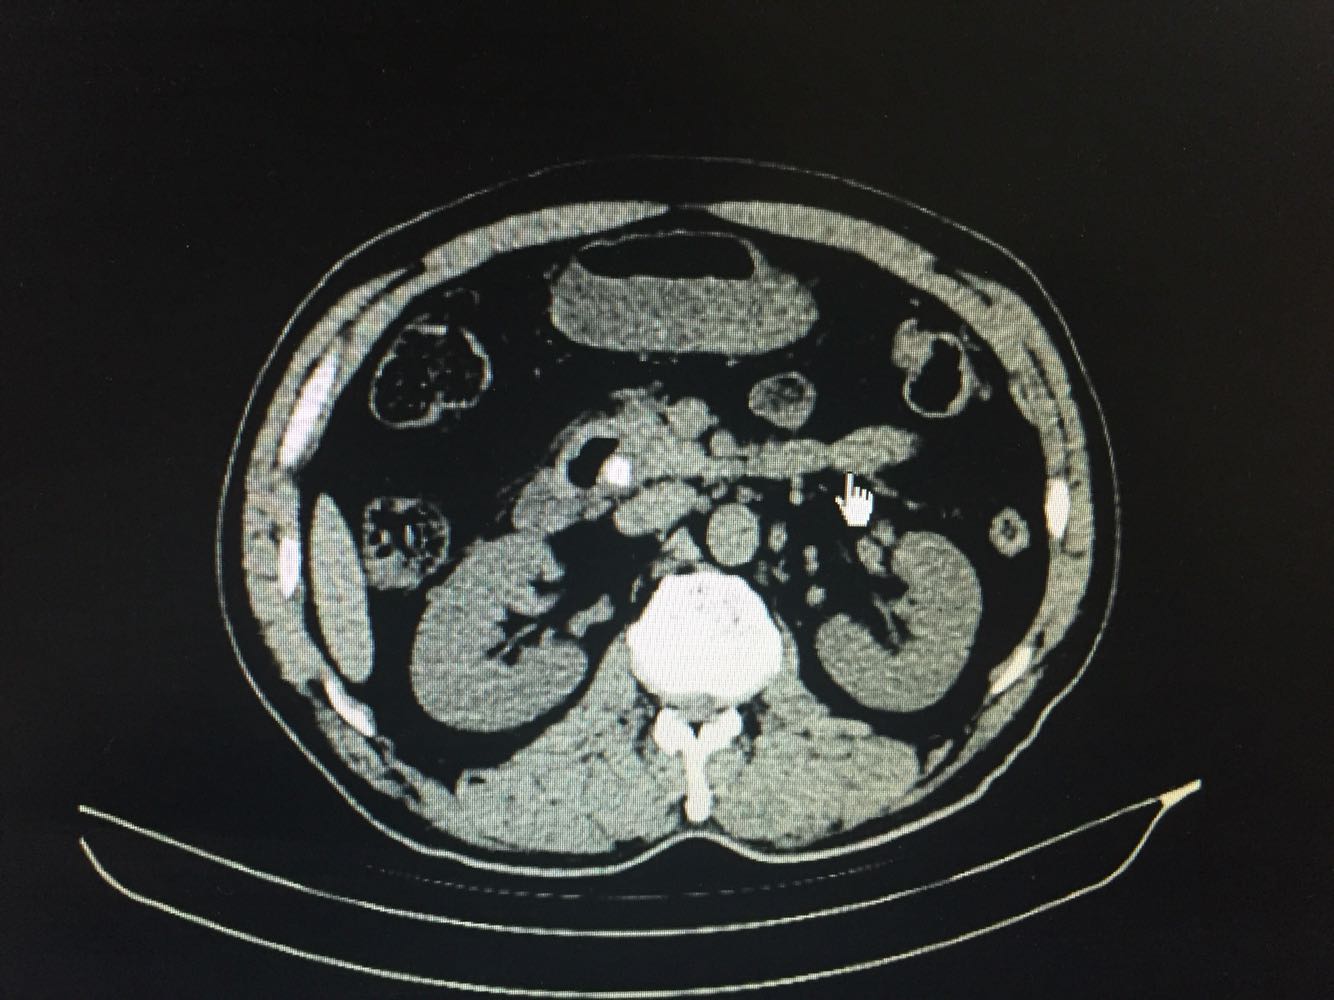

巩膜及皮肤黄染,上腹部稍韧,深压痛,余无明显异常。 上腹部CT提示胆总管扩张伴下端结石,胆囊炎症改变。血生化提示胆红素升高,以直接胆红素为主,转氨酶明显升高。

微创手术确实给病人带来很多受益 术前阅片见下端结石梗阻 术中取石很顺利 出于保险起见 还是没有直接缝合胆总管 留置了T管